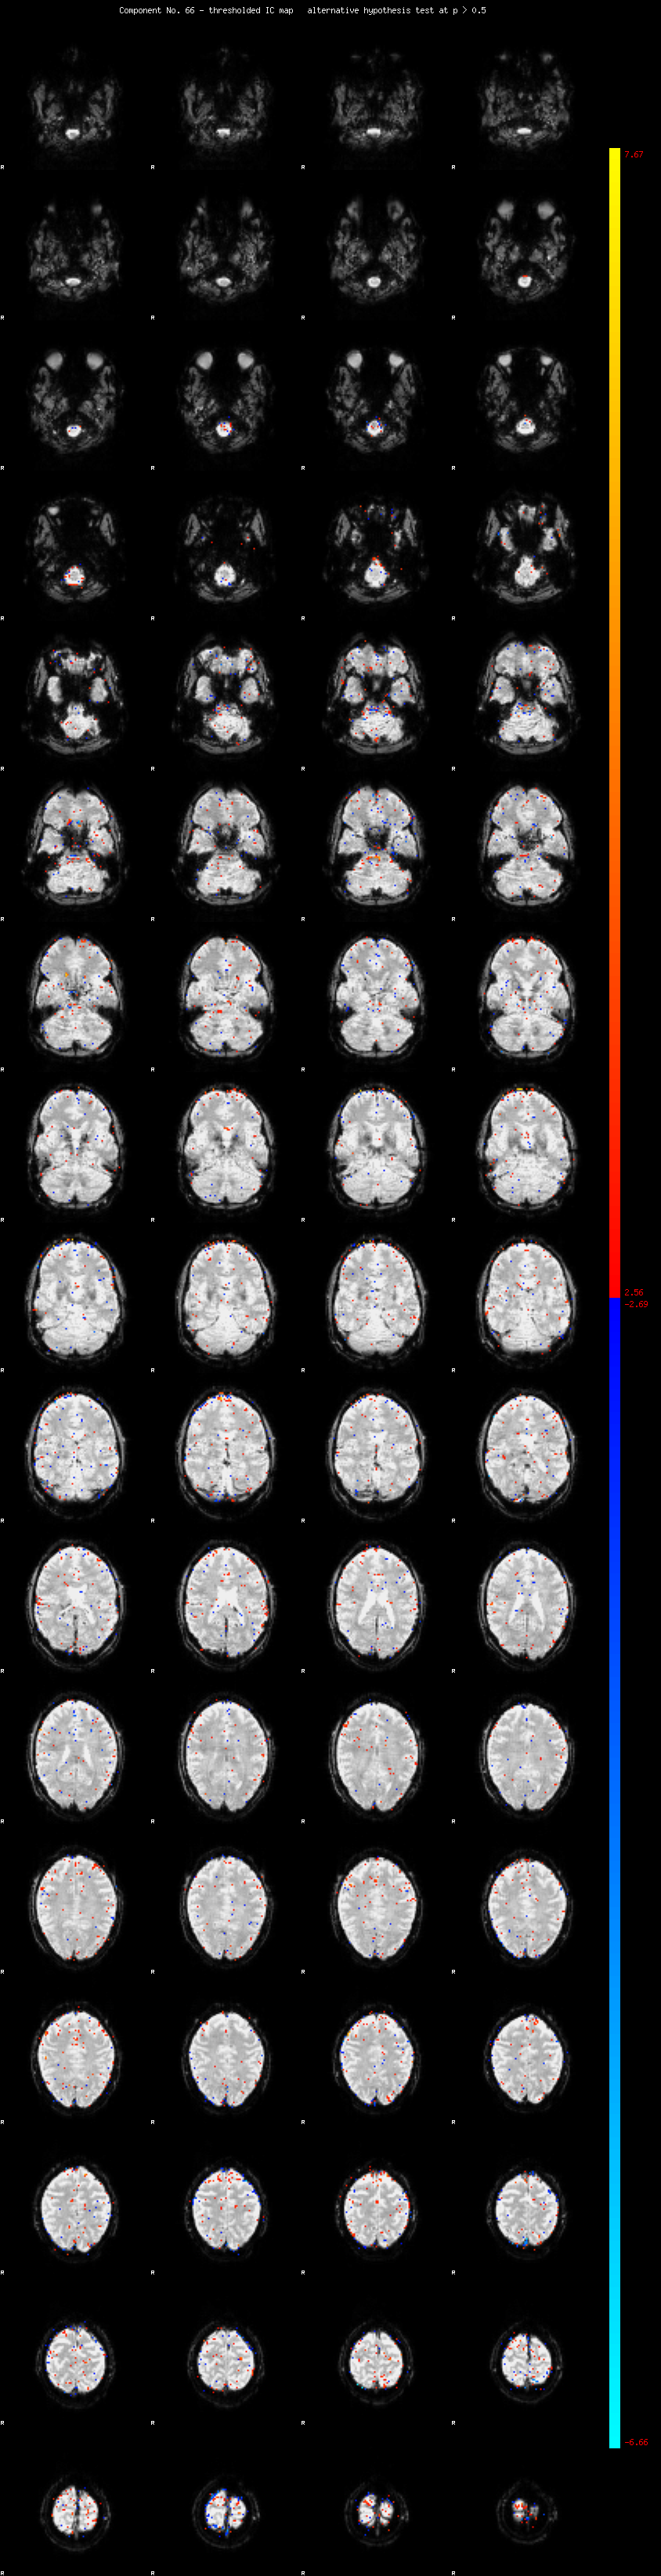

MELODIC Component 66

0.82 % of explained variance;     0.54 % of total variance